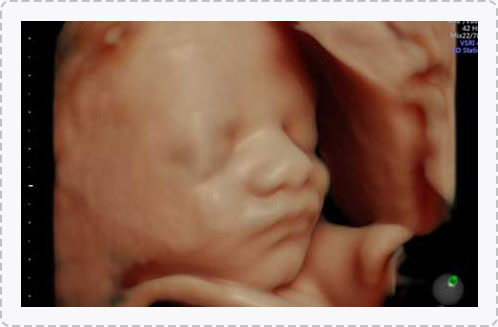

四维彩超优异的图像分辨率,能在四维空间内展现立体的心脏结构和功能,不仅能够检测高危孕妇的心脏状况,h's检查胎儿心脏发育情况。

四维彩超具备一整套成熟的胎心成像技术,支持从胎儿心脏结构到心功能的专业分析,是胎儿心脏检测评估领域的技术。双平面成像技术可实时观察胎心结构和血流变化,帮助临床医生及时作出诊断。

一般情况下四维彩超的检查时间是孕22-28周,这段时间检查,胎儿大小适合,羊水适中,胎儿活动度大,体表也比较丰满,有利于胎儿四维超声成像和畸形筛查,是合适的检查时期。